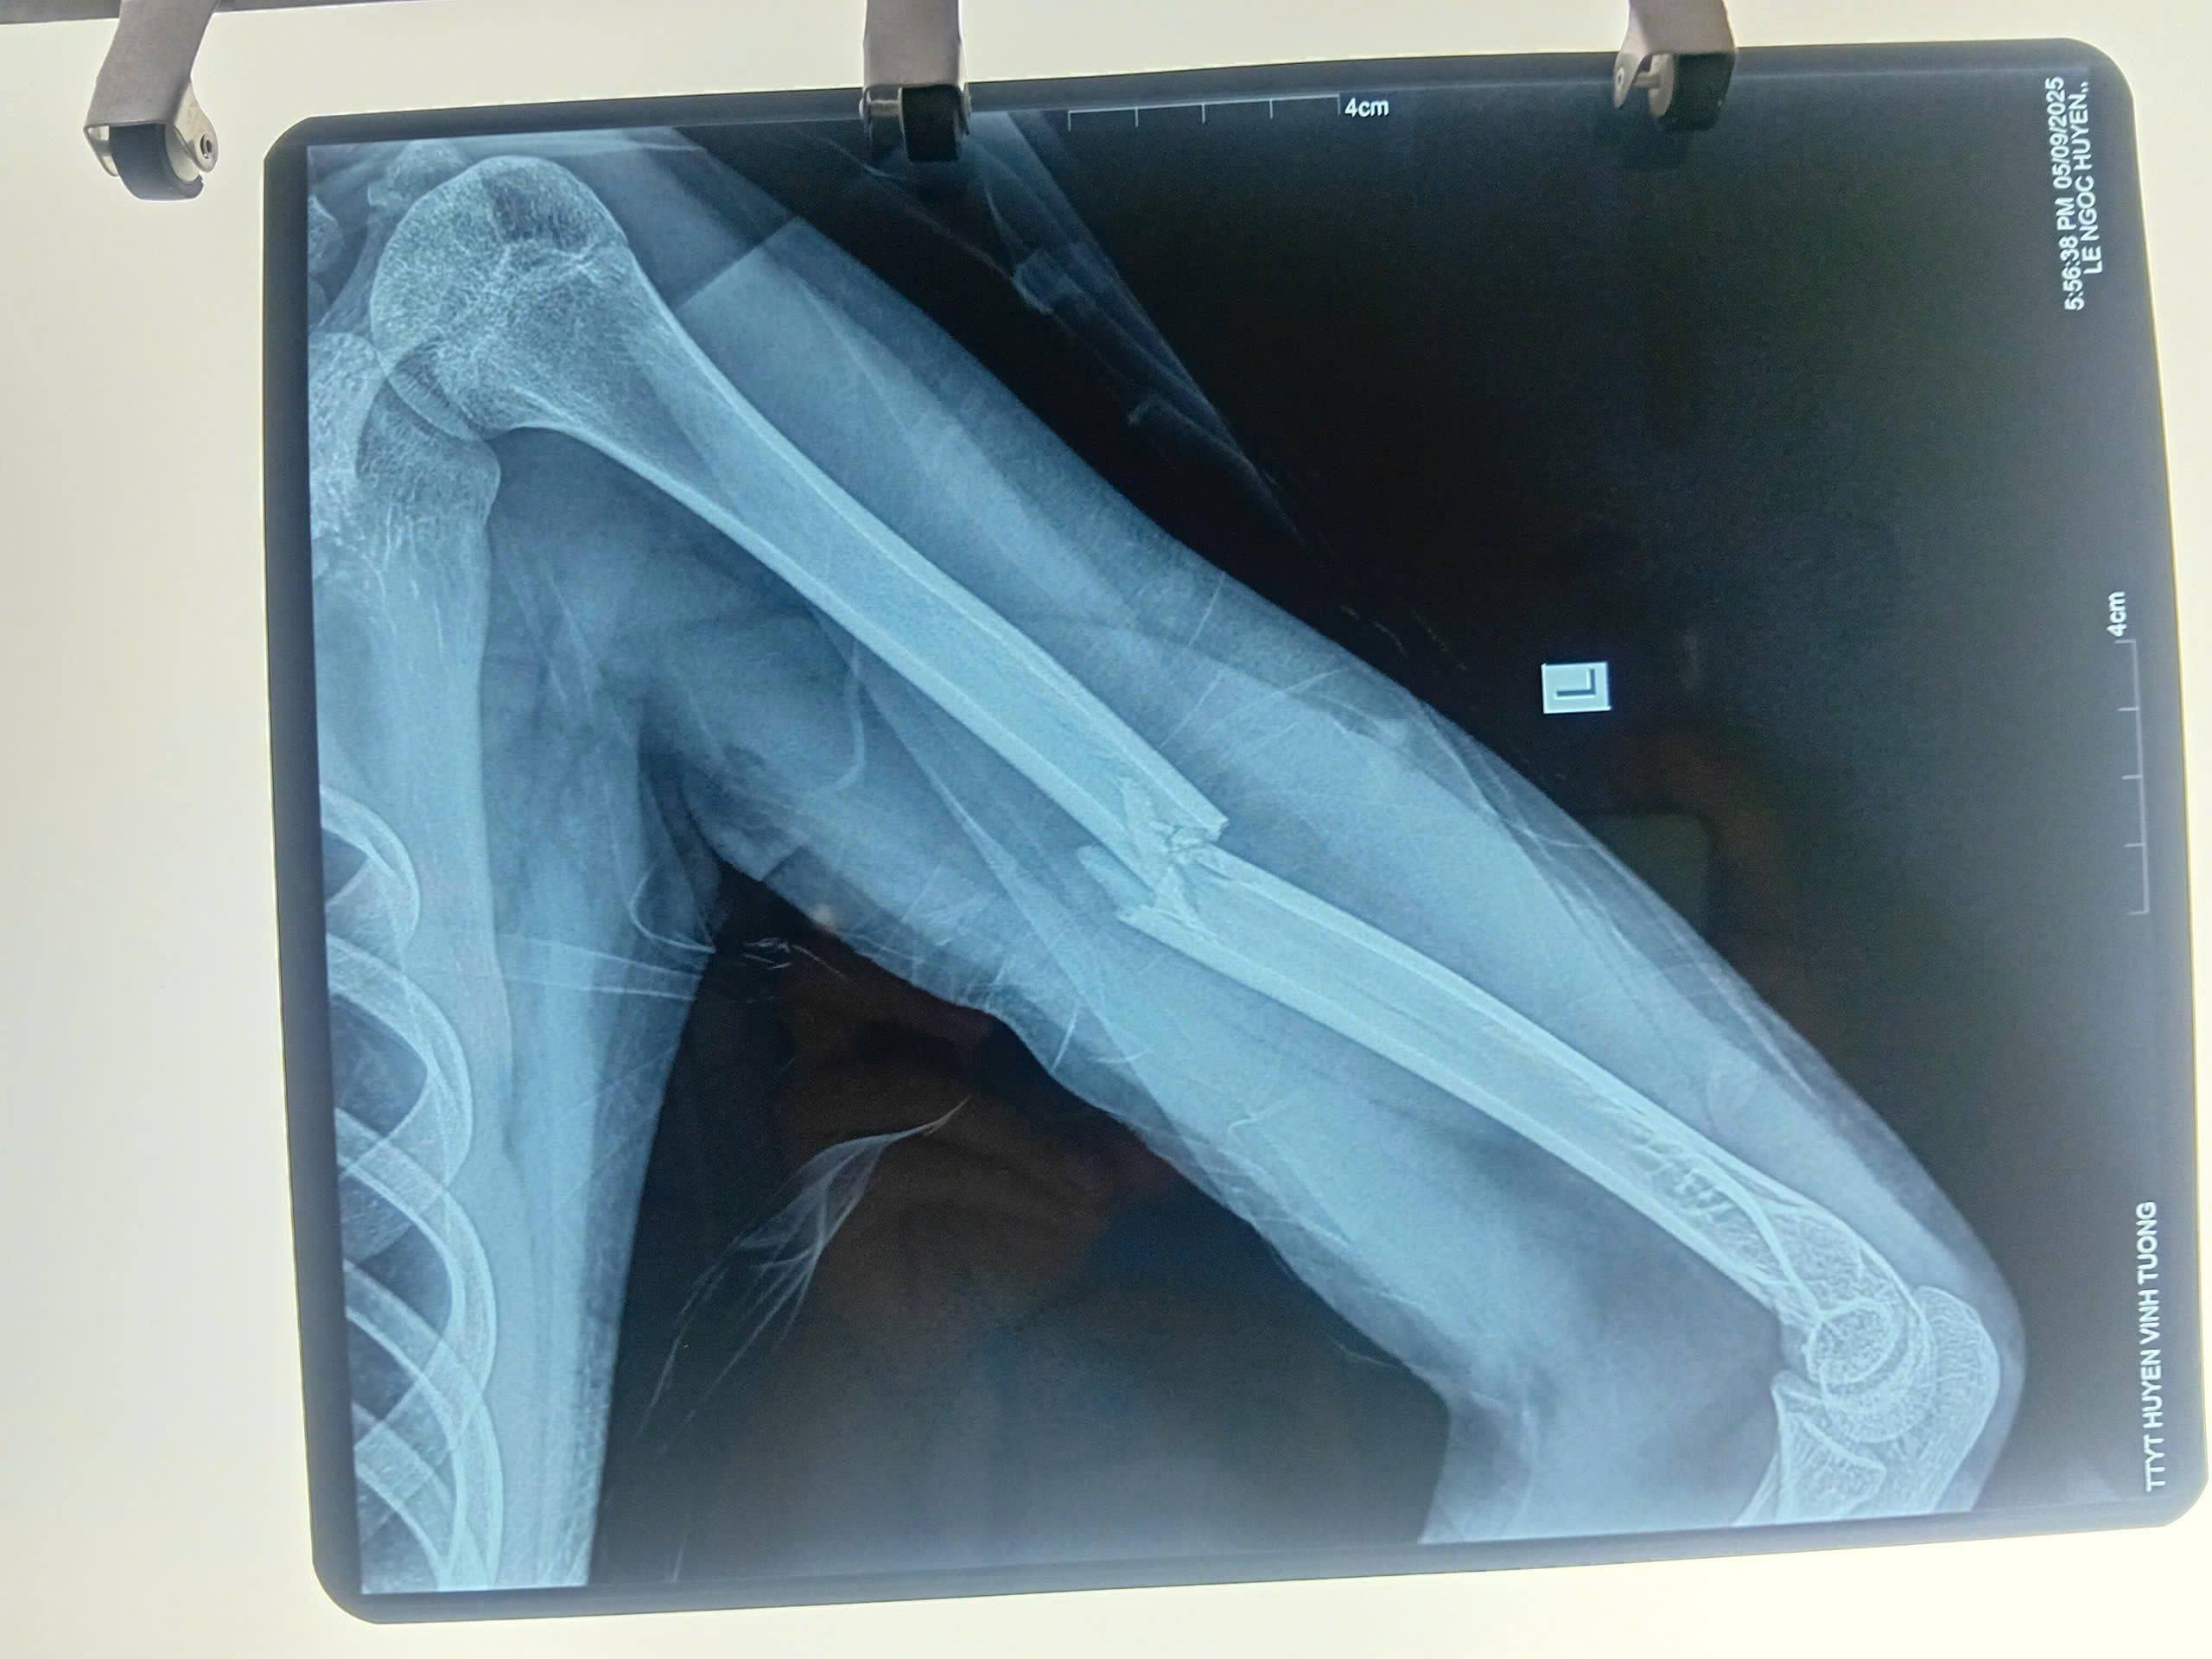

Bệnh nhân L.T.N.H, 16 tuổi, trú tại xã Thổ Tang (Phú Thọ) nhập viện trong tình trạng đau, sưng nề, biến dạng và hạn chế vận động tay trái.

Các kết quả cận lâm sàng cho thấy, bệnh nhân bị gãy 1/3 giữa xương cánh tay trái. Ekip phẫu thuật do bác sĩ Chuyên khoa II Vũ Xuân Trường, Phó Giám đốc Trung tâm y tế khu vực Vĩnh Tường chủ trì đã quyết định và tiến hành phẫu thuật đặt nẹp vít cho bệnh nhân.

Sau khoảng 1 tiếng ca phẫu thuật thành công. Trục xương cánh tay của bệnh nhân được nắn chỉnh thẳng trục và cố định vững chắc. Mạch quay bắt rõ, da đầu chi hồng, ấm; vận động và cảm giác bàn tay bình thường, cho thấy chức năng thần kinh cánh tay được bảo tồn.